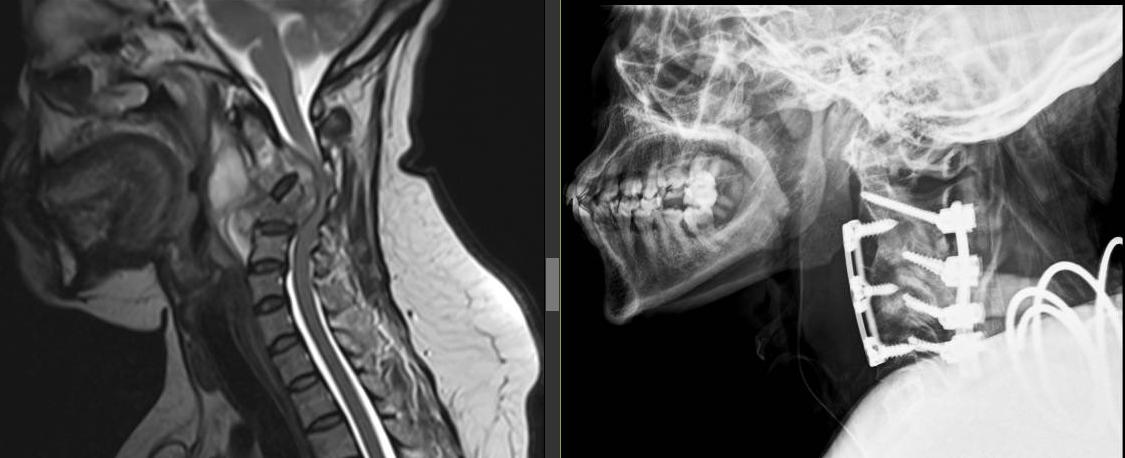

The Centre For Neuro-Oncologic and Spine Surgery (CNS) is a Gaborone-based Neurosurgical practice providing expert care for a wide scope of emergency and elective services. We have a special interest in minimally invasive brain tumor surgery and spine surgery.

Dr. B. A. Kgaodi is a neurosurgeon with subspecialty fellowship training in Spine surgery and a special interest in endoscopic pituitary surgery.

We have a special interest in minimally invasive brain tumor surgery and spine surgery.

Very highly professional, friendly, and exceptional at their work. A truly 5-star experience. I am now recovering very well following my cervical surgery performed by Dr. Kgaodi.